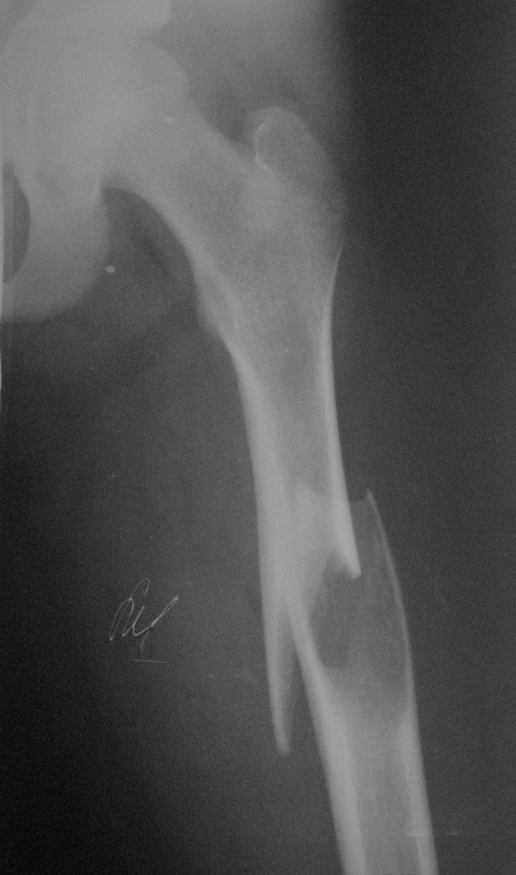

По неотложке в наше отделение попал мальчик 13 л. с патологическим переломом бедра.

Консультирован нашим главным детским ортопедом. Выставлен диагноз: солитарная костная киста. В профильное отделение переводить мальчика родители не хотят (мне причина не известна). Рекомендован ЧКОС закрыто без костной пластики. Какие подходы используются в профильных отделения ваших клиник при даной патологии? Спасибо.